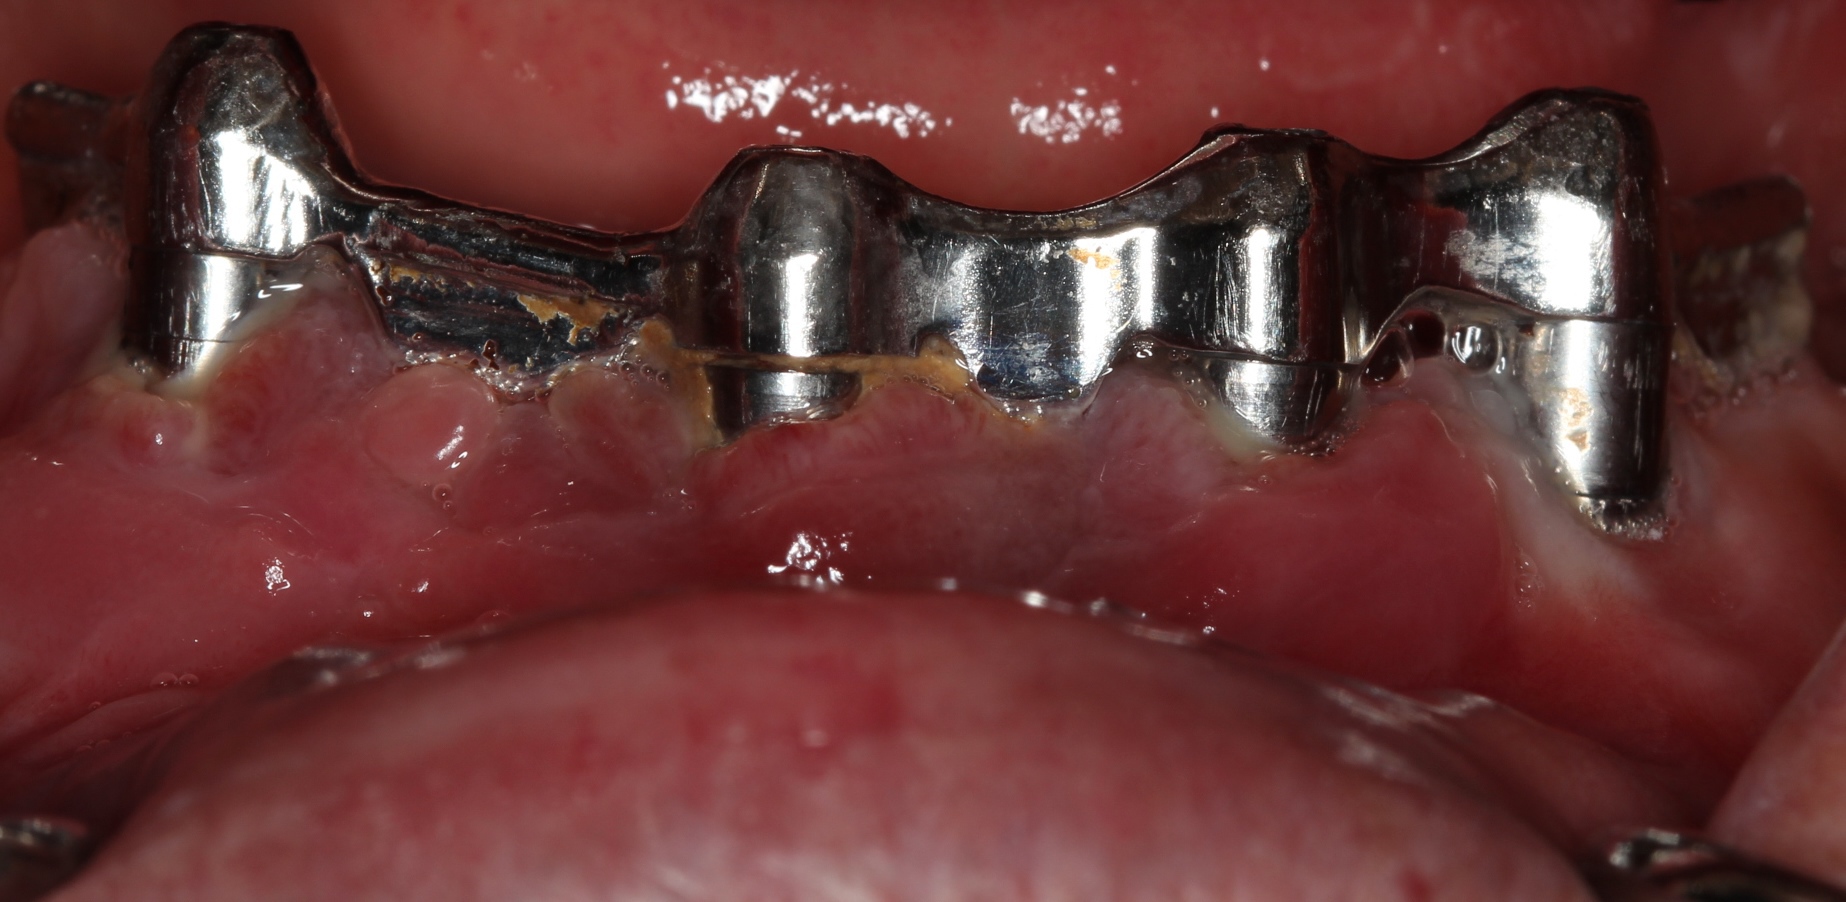

Methods: Fifty-seven years old systemically healthy non-smoker male was referred to the Department of Periodontology, Abant Izzet Baysal University from a special clinic with complaint of pain, bleeding of gums, supuration around implants and bad breath. Clinical and radiological examination revealed as peri-implantitis in mandibular anterior region (probing pocket depht (PPD) >7 mm with supuration and bleeding on probing, marginal bone loss > 1/3 implant length) for each of four implants and gingival overgrowth around maxillar implants. While removing the prosthetic abutments, one implant was lost. Peri-implant therapy included debridement of implant surfaces using titanium curettes combined with systemic antibiotics and chlorhexidine. Gingival conturing was performed using Diode laser before prosthetic rehabilitation. Oral hygiene instructions were given to the patient and peri-implant clinical parameters were recorded at 1sth, 3th, 6th and 12th months. Four months after healing of peri-implant tissues prosthetic rehabilitation was completed.

Results: There was no bleeding on probing and supuration. Radiological bone fill around implants were seen and PPD was 4 mm. During the follow periods, these results were maintained and patient had no complaints about the prosthetic rehability.